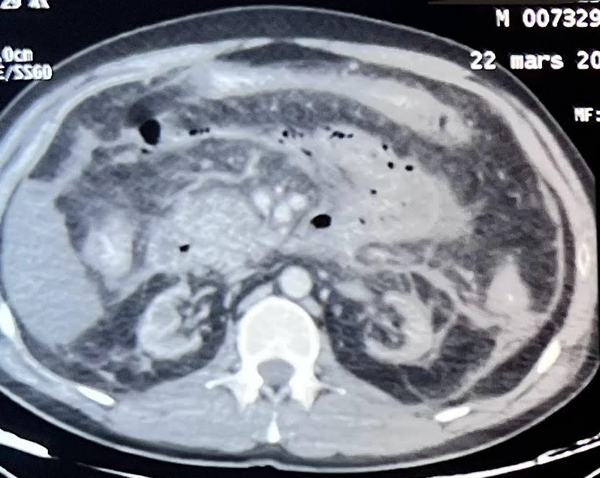

Two weeks later, his clinical condition worsened, and he developed severe sepsis. The abdominal CT scan (Figure 2) showed a progression to stage E pancreatitis, with increasing necrotic flow, requiring urgent scanno-guided drainage. Sadly, the patient died within 24 hours from septic shock secondary to the pancreatitis.

Figure 2.Abdominal CT scan showing necrotic flow (case 1)